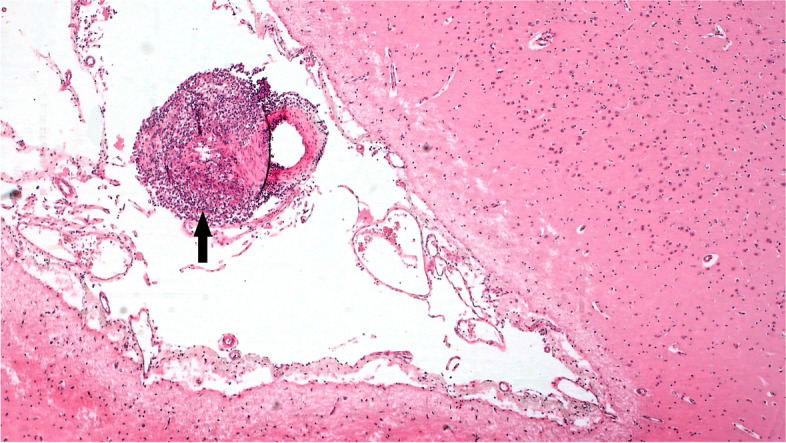

Case presentation: Using similar methods this case study reports on the findings of the first reported cases in an Irish Flock of MCF- like systemic necrotizing vasculitis in sheep associated with OvHV-2. Sheep A, a 16-month-old Texel-cross hogget displayed signs of ill- thrift, Sheep B, a nine-month-old Belclare-cross lamb, was found dead having displayed no obvious symptoms. Both cases occurred on the same farm, however the animals were not related. Lymphohistiocytic vasculitis of various tissues was the predominant histopathological finding in both animals.

Conclusion: By combining histopathology, PCR and in-situ hybridisation results, MCF- like systemic necrotizing vasculitis associated with OvHV-2 has been diagnosed for the first time in an Irish flock.